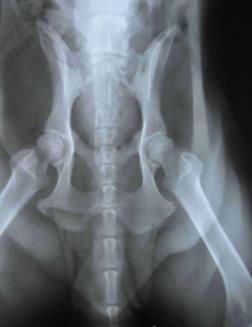

以下照片为62kg大型犬骨盆拍片效果图,如果您对宠物X光机感兴趣,欢迎致电咨询。